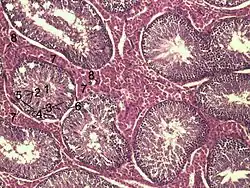

![]() Histological section through testicular parenchyma of a boar. 1 Lumen of tubulus seminiferus contortus, 2 spermatids, 3 spermatocytes, 4 spermatogonia, 5 Sertoli cell, 6 Myofibroblasts, 7 Leydig cells, 8 capillaries | |